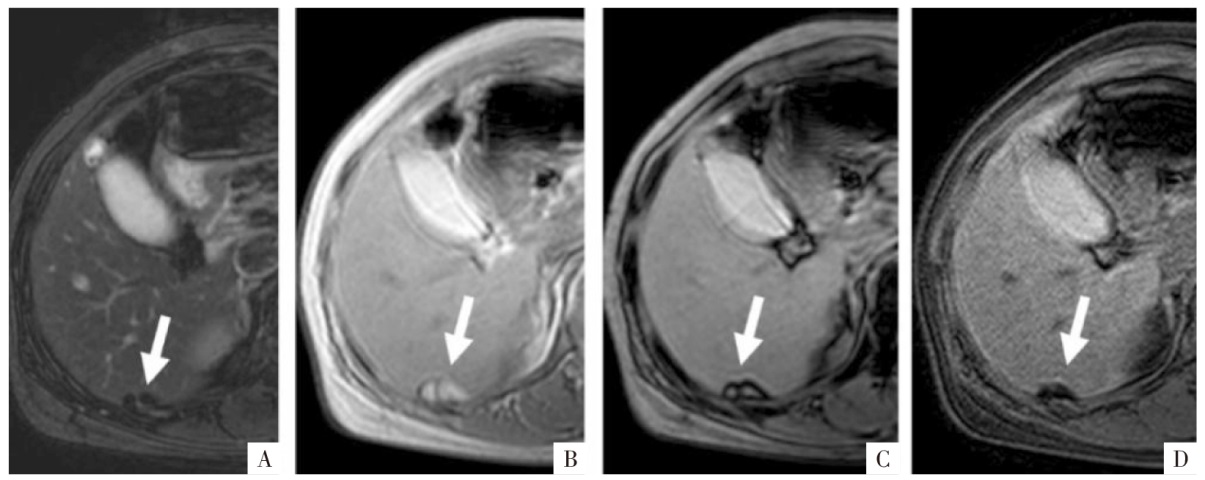

图3

脂肪组织MRI表现。病人女,50岁,上皮样血管平滑肌脂肪瘤,病灶内含有小块的脂肪组织(粗、细箭头)。A、B、C图分别为三维GRE序列T

1

WI同相位、反相位、水像(即脂肪抑制像),显示相应脂肪组织在同相位(A)为高信号,反相位(B)中心为高信号,周边环形勾边,脂肪抑制像上病灶信号减低(C)。

图4

病人女,42岁。手术病理证实为肝左外叶上皮样血管平滑肌脂肪瘤(细箭),内有直径约5 mm小块脂肪(粗箭)。A、B图分别为厚层同相位及反相位影像,层厚6 mm,矩阵256×180,同相位影像上含脂区域呈高信号(A),反相位影像上为含脂区域整体信号衰减(B),易误判为脂肪变性;C图为薄层高分辨力反相位影像,层厚3 mm,矩阵320×288,含脂区域中心仍呈高信号,周围可见勾边,为小脂肪块的典型表现。